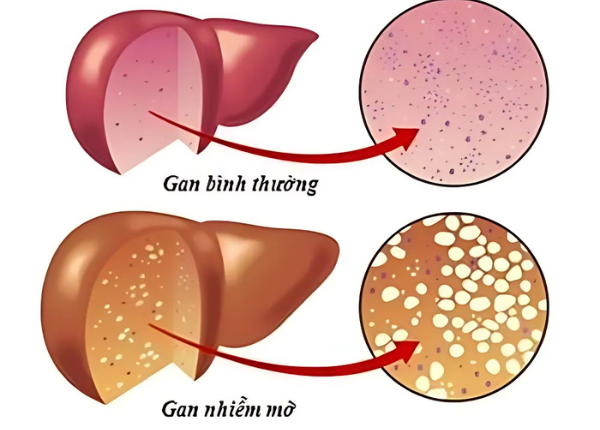

Gan nhiễm mỡ là bệnh gì? Nguyên nhân và dấu hiệu nhận biết

Gan nhiễm mỡ là tình trạng mỡ tích tụ bất thường trong tế bào gan, chiếm trên 5% khối lượng gan. Đây là một rối loạn chuyển hóa phổ biến, thường diễn tiến âm thầm và ít gây triệu chứng rõ rệt ở giai đoạn đầu. Tuy nhiên, nếu không được kiểm soát, gan nhiễm ...

Phân biệt gan nhiễm mỡ không do rượu và gan nhiễm mỡ do rượu?

Gan nhiễm mỡ không do rượu và gan nhiễm mỡ do rượu là hai thể bệnh lý thường gặp, nhưng rất dễ bị nhầm lẫn nếu không được chẩn đoán kỹ lưỡng. Cả hai đều là tình trạng tích tụ mỡ trong gan, vượt quá 5% trọng lượng gan, nhưng lại có nguyên nhân, tiến ...